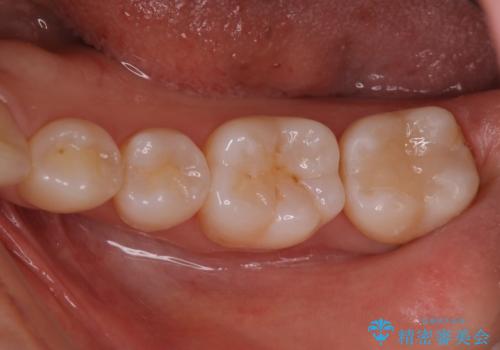

銀歯を白いセラミックに変えたい セラミックインレー

セラミックインレーで治療を行いました。

口の中にチラつく銀歯は適合の良いセラミックインレーでやり替えることで綺麗にやり替えることができます。